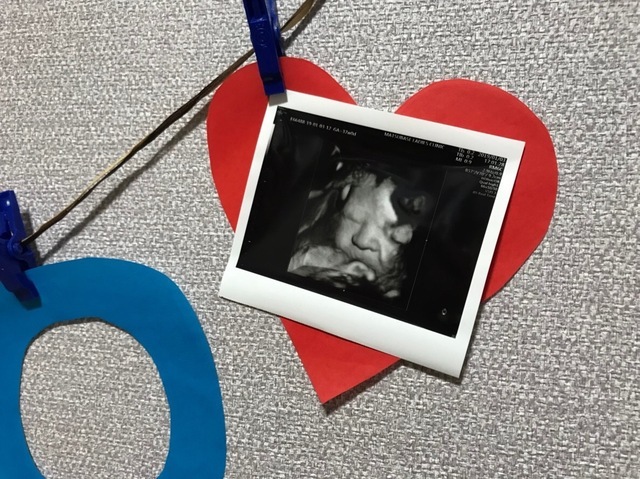

37週0日(37w0d・女の子)|aada1254さん(25歳)

エコー写真撮影時のエピソード:

顔がここまでハッキリと分かるエコー写真は初めてだったので、とても感動的でした。色々な人に見せてあげたい1枚です(^^)

正産期に入り出産も待ち遠しいこの頃なので、実際どんな顔の子が出てくるのか、今から楽しみです!